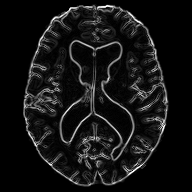

Diffeomorphic deformable multi-modal image registration is a challenging task which aims to bring images acquired by different modalities to the same coordinate space and at the same time to preserve the topology and the invertibility of the transformation. Recent research has focused on leveraging deep learning approaches for this task as these have been shown to achieve competitive registration accuracy while being computationally more efficient than traditional iterative registration methods. In this work, we propose a simple yet effective unsupervised deep learning-based multi-modal image registration approach that benefits from auxiliary information coming from the gradient magnitude of the image, i.e. the image edges, during the training. The intuition behind this is that image locations with a strong gradient are assumed to denote a transition of tissues, which are locations of high information value able to act as a geometry constraint. The task is similar to using segmentation maps to drive the training, but the edge maps are easier and faster to acquire and do not require annotations. We evaluate our approach in the context of registering multi-modal (T1w to T2w) magnetic resonance (MR) brain images of different subjects using three different loss functions that are said to assist multi-modal registration, showing that in all cases the auxiliary information leads to better results without compromising the runtime.

In this paper, we propose a novel unsupervised multi-modal image registration approach to tackle the problem of registering images of different subjects (inter-subject) acquired by two different imaging modalities (T1w, T2w MR images). We are integrating ideas from the work of Pluim et al. [10] that combines mutual information with a term based on the magnitude and direction of the image gradients to rigidly register 3D MR, CT and PET images, the work of Qin et al. [11] that uses segmentation maps as auxiliary information to guide the task of motion estimation and the work of Zhe Xu at al. [12] that performs unsupervised multimodal CT-MR image registration leveraging the deformation fields estimated from a branch aiming to align the original fixed and moving images and a branch aiming to align the corresponding gradient intensity maps.

Similarly, we propose to make use of the edge maps extracted the images, as a complementary signal, to aid the training of registration network. The main assumption is that since the anatomy depicted by the two modalities is very similar, the edge maps can serve as a geometrical constraint. At the same time,

the edges are less \saymodality dependent, a property that is very useful in the case of multi-modal registration due to the fact that we do not have to deal with the complicated intensity relationship between the modalities. This simple, yet, effective technique shows that the edge signal can be beneficial for multi-modal image registration.

2.1 Edge Maps

As stated above, the edge maps extracted from multi-modal images can be a useful auxiliary information to guide multi-modal image registration. Specifically, the edge map of a 2D (but easily extensible to 3D) image can be easily obtained by calculating the central differences between adjacent pixels.

We decided to only use the gradient magnitude because it is sufficient to depict the underlying geometry and discard the information relating to the edge direction. The part of the network that handles the edge maps is more sensitive in capturing the structural dependencies between the two images, rather than the complex intensity relationships, and hence serves as a spatial constraint assisting the task of image registration. In practice, the edge maps are given as input to an encoder which adopts the same architecture as the one that handles the images.

We evaluate our work on the task of inter-subject brain MRI registration on T1w-T2w images. For this purpose, we decided to use the Cambridge Centre for Ageing and Neuroscience (CamCAN) dataset [20], [21]. The dataset consist T1w and T2w MR 3D volumetric images of 310 subjects, with isotropic spatial resolution. In our work we only use 2D slicse of the volumetric image cropped to the size of . Although this work could directly be transferred in 3D, we use 2D images as a proof-of-concept, due to the large computational requirements when using 3D images. After affine alignment to a common MNI space using ANTs [22], the images are skull-stripped using ROBEX [23] and bias-field corrected using the N4 algorithm in SimpleITK [24]. For evaluation, we also acquired the segmentation of 138 cortical and sub-cortical structures (grouped into 5 groups) automatically using MALPEM [25].